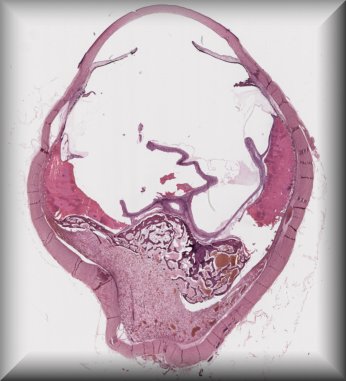

Thomas J. Cummings (Durham, North Carolina): 54-year-old male with multiple systemic infections underwent enucleation after 2 months of pain, redness and acute loss of vision. |